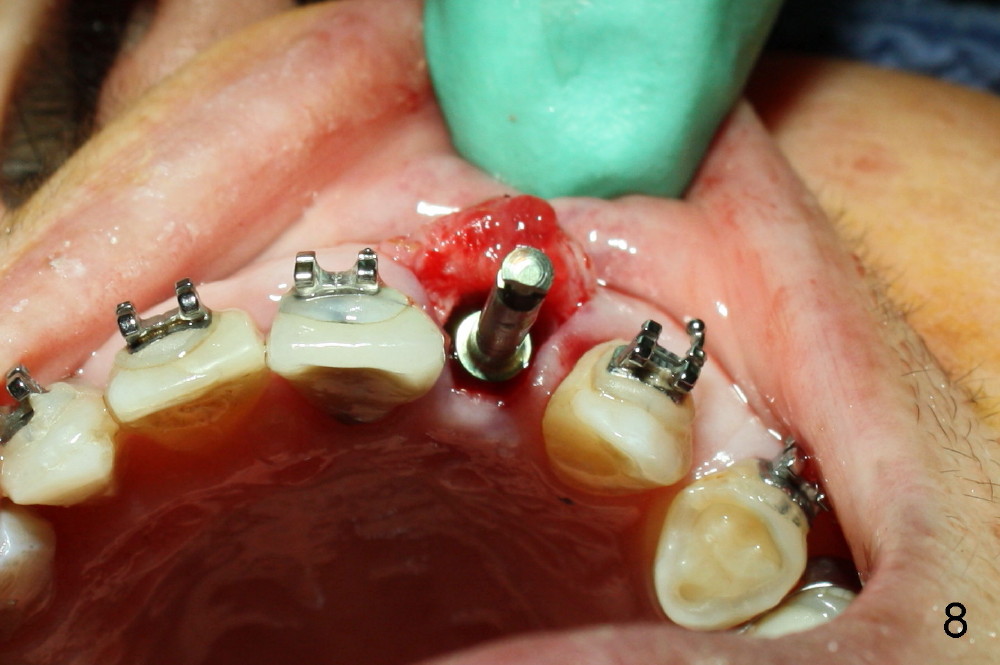

The 2.5 mm reamer is inserted as planned (following the contour of the alveolus (4)). Although the reamer (Fig.7 R) is palatal and there is a gap buccally (*), the handle of the reamer tilts buccally (Fig.8). A straight wall is created by using 2.5 mm reamer (Fig.9). A tapered implant is inserted (3.8x14 mm with apical diameter 2.4 mm, Fig.10). It is supposed to have high torque, but this implant is placed with a knob driver, probably due to osteoporosis. The dilemma is that the patient insists upon immediate provisional. If a tap driver were used, low torque would be found before implantation.